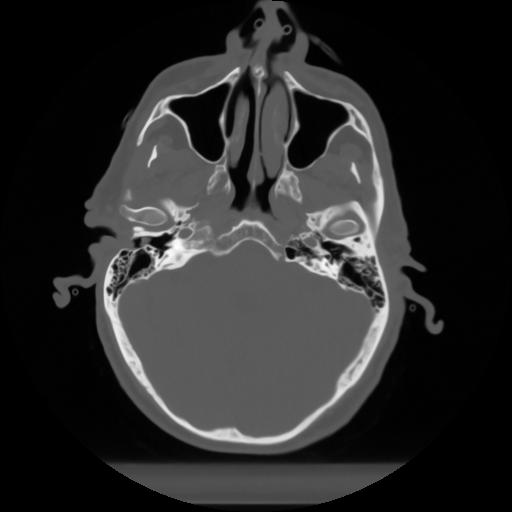

10 P.BLANDAS,,Axial,2.0,P.BLANDAS,,